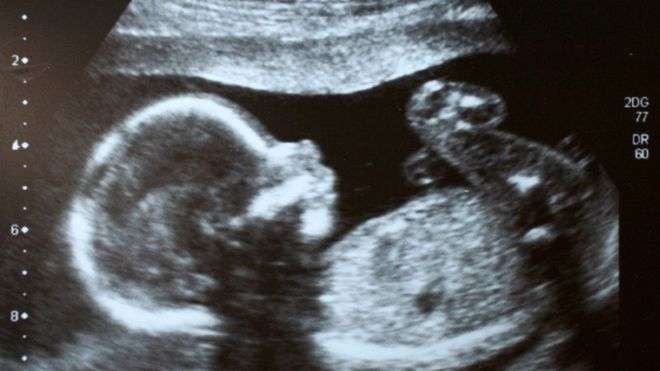

İngiltere'de bağımsız bir tıbbi gözlemci kurumu, bir insan embriyosunu genetik olarak değiştirme konusunda etik olarak bir sakınca bulunmadığına karar verdi.

Genom düzenleme, embriyolardaki, spermlerdeki ya da yumurtalardaki sorunlu kodları kalıcı olarak değiştirerek ya da silerek, genetik hastalıkların önüne geçilmesi amaçlı kullanılabilir.

Aynı zamanda tasarım bebeklerin önünü açacağı endişesiyle etik tartışmaları da beraberinde getiriyor.